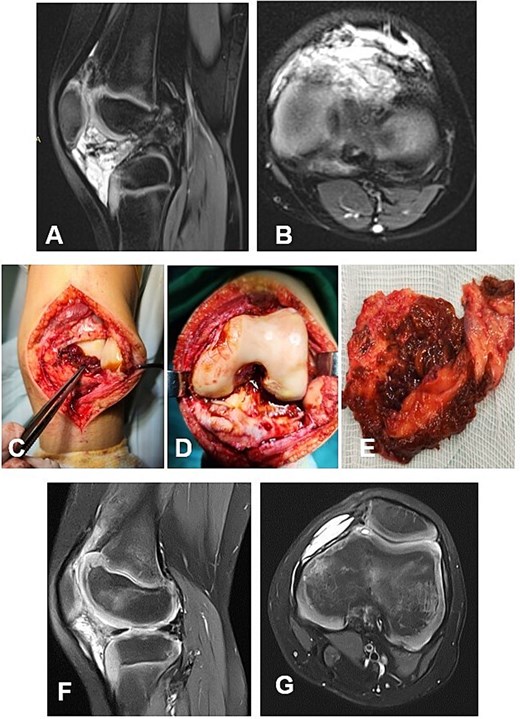

A 13-year-old female patient presented with a nodular tenosynovial giant cell tumor (N-TGCT) involving the medial posterior femoral recess. The clinical course was characterized by intermittent knee pain and swelling persisting for ~12 months. MRI demonstrated an intra-articular, well-defined lobulated lesion with posterior mediocentral localization, causing lateral displacement of the neurovascular bundle (Fig. 5A and B). A complete excision of the lesion was achieved through a posterior synovectomy, performed sharply and within macroscopically healthy synovial margins (Fig. 5C and D). At 12-month postoperative follow-up, the patient was asymptomatic, with full range of motion and no MRI evidence of local recurrence. The ligamentous apparatus remained intact.

Case 4. (A and B) Preoperative Sag and Ax MRI TSE PD FS—a lobulated intra-articular neoplasm with a posterior mediocentral localization, displacing the neurovascular bundle laterally. (C and F) Macroscopic appearance of the N-TGCT measuring 3 × 1 × 2 cm, in situ and after excision. (C) Posterior synovectomy performed with lateral retraction of the m. gastrocnemius medialis. (D) The joint after synovectomy, showing grade I chondral changes according to the Outerbridge classification. (E) Reconstructed fibrous capsule. (E and F) Postoperative 12-month sagittal and axial MRI (TSE PD FS) demonstrates no evidence of recurrence of the resected neoplasm. (G and H) PD FS, proton density weighting with fat suppression; TSE, turbo spin echo.